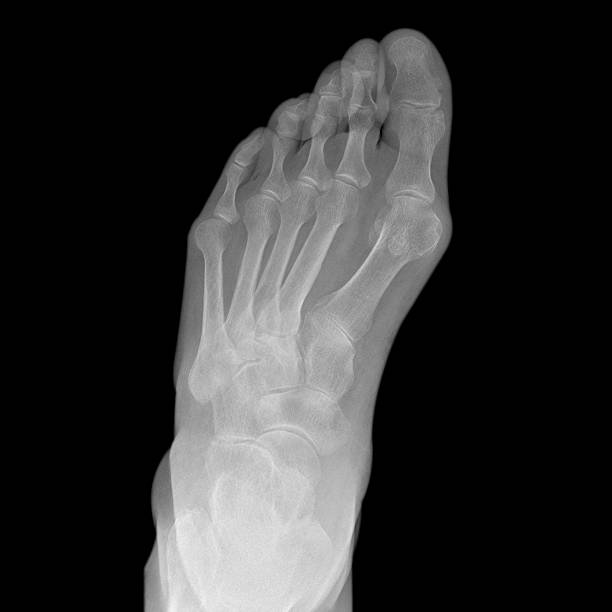

발뒤꿈치가 아픈 이유 다섯 번재는 발목 터널 증후군입니다. 내측 복사뼈와 발뒤꿈치 뼈 사이의 족근관을 관통하는 후경골 신경이 눌리거나 손상되면 저림, 작열감 등을 느끼게 됩니다. 이때는 신경 압박에 의한 통증이기 때문에 앞서 언급한 연조직 손상과 달리 통증의 위치가 명확하지 않고 신경 경로를 따라 퍼지는 특성을 갖고 있습니다.